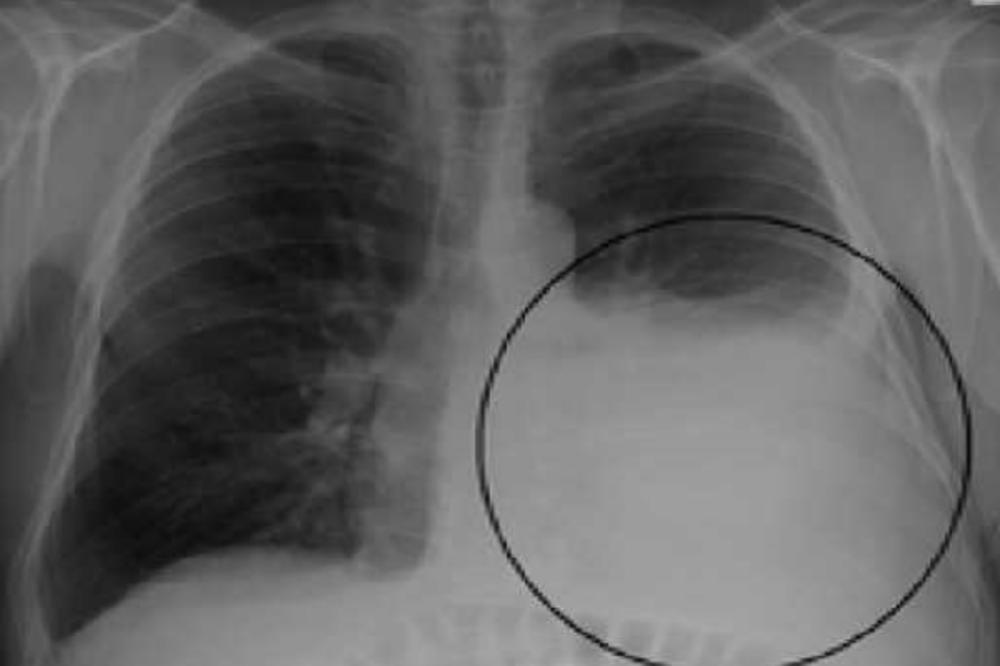

Umesto ružičaste boje, pluća pedesetdvogodišnjeg muškarca iz Kine bila su skroz crna. Hirurzi su ih snimili tokom eksplantacije budući da je muškarac preminuo i donirao organe. Lekari u Kineskoj bolnici Wuxi u Đansu izvadili su pluća čoveku koji je preminuo zbog otkazivanja pluća, a video koji su snimili pogledalo je više od 25 miliona ljudi na društvenim mrežama. Mnogi su komentarisali da se radi o najboljoj antipušačkoj kampanji, a bolnica je uz video postavila pitanje - Imate li još uvek hrabrosti da zapalite cigaretu? Pacijent je pre smrti želeo da daruje organe, ali lekari su ubrzo uvideli da ih nikako ne mogu iskoristiti.

- Pacijent nije išao na CT pre smrti. Proglasili su moždanu smrt, a nedugo nakon toga njegova pluća su bila donirana. Kada smo ga otvorili, shvatili smo da organe ne možemo iskoristiti. Mi Kinezi volimo da pušimo. Bilo bi nepraktično reći da ne želimo da prihvatimo pluća svih pušača koji doniraju organe, ali postoje jasni standardi - ističe dr Čen objašnjavajući kakva pluća dolaze u obzir - Prihvatili bismo pluća mlađih od 60 godina, a prihvatljive su nam sitne infekcije i relativno uredan rendgenski nalaz. Ako je o takvim plućima reć, uradili bismo transplataciju. Ističu da je pacijent najverovatnije patio od plućnog emfizema - bolesti koja vodi do upale organa, kada pluća gube elastičnost, pa se time otežava disanje.